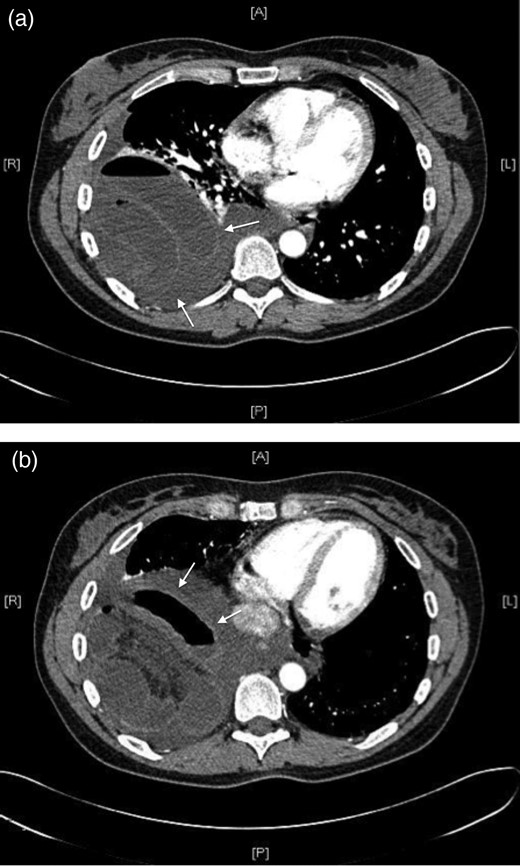

In light of her clinical presentation she was suspected of having suffered a pulmonary embolism. A CTPA was performed which revealed a large defect in the right hemi diaphragm and small bowel in the thorax with evidence of small bowel obstruction (see Fig. 1).

(a) and (b) Large right-sided diaphragmatic hernia with obstructed bowel (white arrows) evident on CTPA.